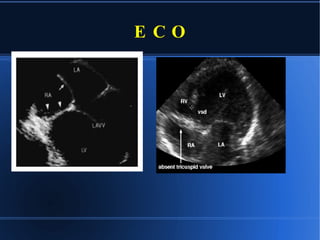

E C O